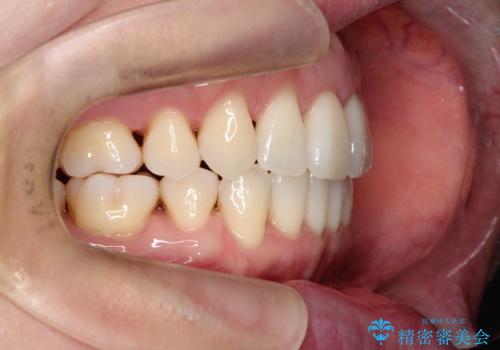

【抜歯ケース】前歯のガタガタをインビザラインで治療

- 前歯のガタガタを主訴に来院されました。

抜歯が必要なケースでしたが、インビザラインでの治療を希望されワイヤーを使用せずに治療を完了しております。